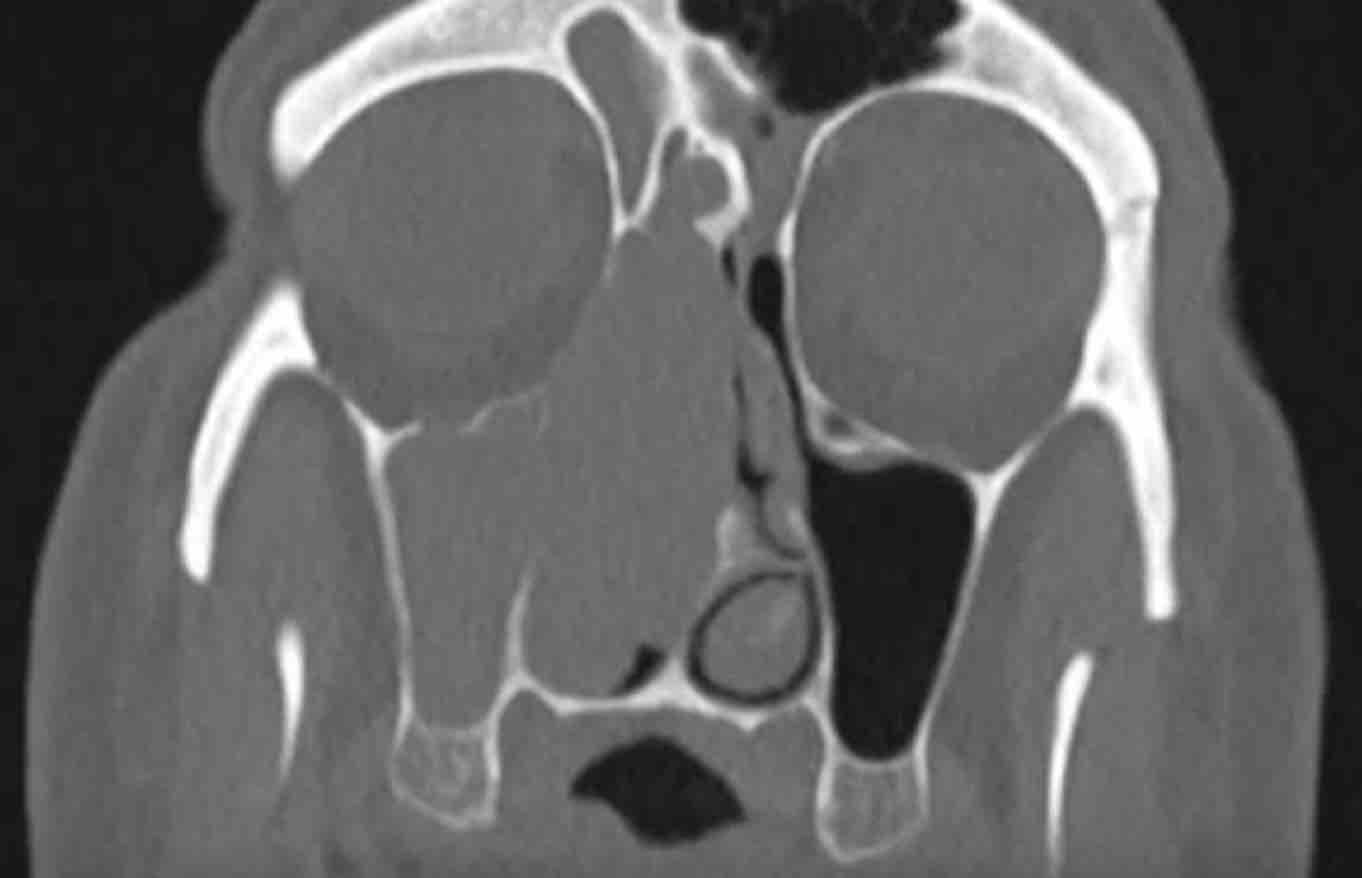

Các hình ảnh này của bệnh nhân nam 75 tuổi có triệu chứng nghẹt mũi và chảy máu mũi.

Hai dấu hiệu cảnh báo là:

- Phá hủy thành trong xoang hàm (mũi tên đen) và vách mũi (mũi tên trắng).

- Bệnh lý hoàn toàn một bên.

Ở bệnh nhân viêm mũi xoang, có thể có giãn rộng và đôi khi thậm chí phá hủy xương, nhưng bệnh lý (hầu như) luôn luôn xảy ra hai bên.